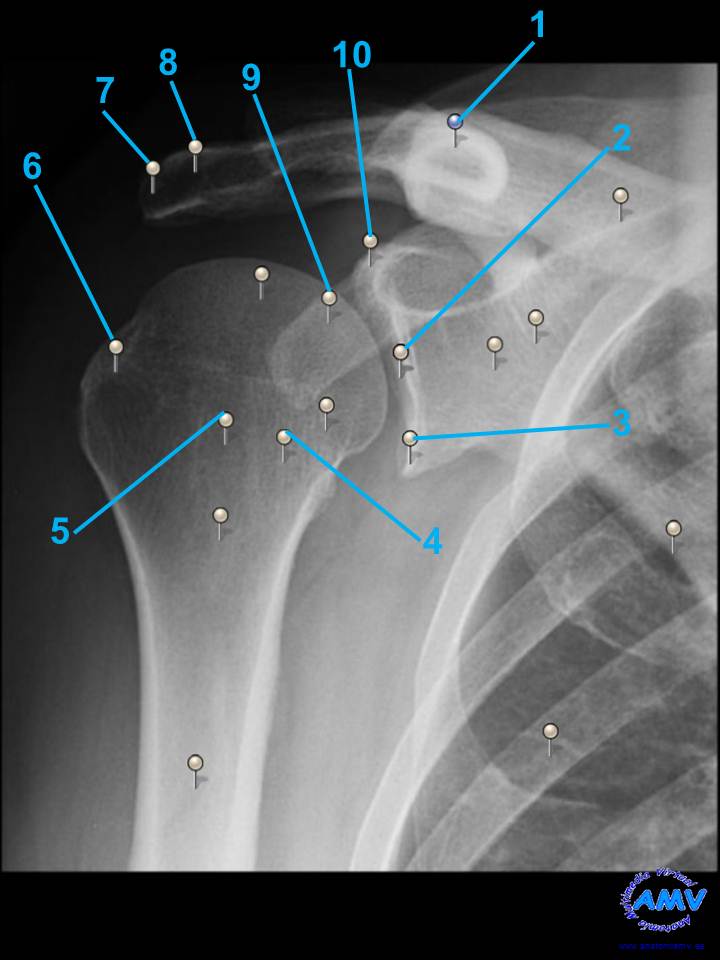

rx_ms_03.jpgIndique que estructura se señala con el número correspondiente:

El nº 1 señala .

El nº 2 señala .

El nº 3 señala .

El nº 4 señala .

El nº 5 señala .

El nº 6 señala .

El nº 7 señala .

El nº 8 señala .

El nº 9 señala .

El nº 10 señala .